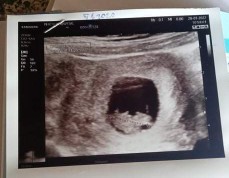

กำหนด9กันยาจ้า ตัวเล็กมีหัวใจเห็นชัดเจนแล้ว 9w